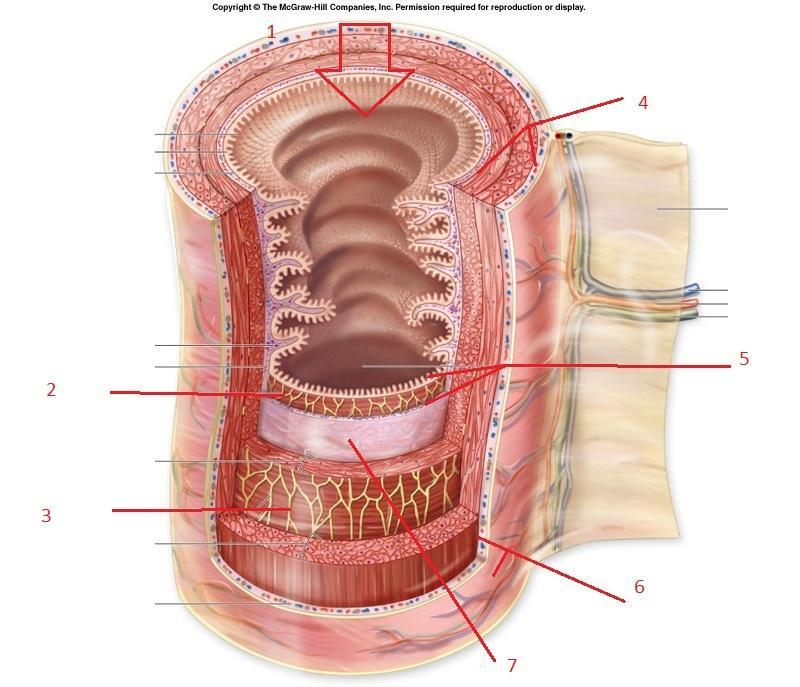

Mucosa

Submuscosa

Inner circular layer (of muscular externa)

Outer longitudinal layer (of muscular externa)

Serosa

Lumen

Villus (s.) Villi (pl.)

Microvillus (s.) Microvilli (pl.)

Lacteal

Goblet cells

Mesentery